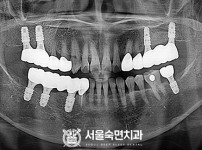

임플란트-전후사진2